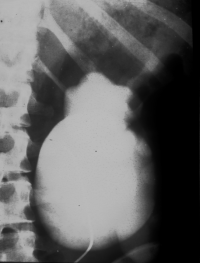

• Abbildung 17: Ureterabgangsstenose mit ausgedehnter Hydronephrose links

4. Resezierter Nierenbeckenanteil und Harnleiterenge

5. Ausscheidungsurogramm nach Ureterabgangsplastik, deutlicher Rückgang des weitgestellten NBKS